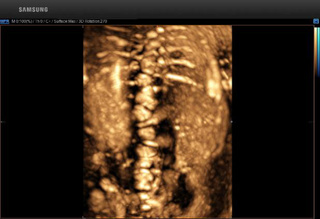

↓↓正常脊柱 ↓↓半椎体畸形